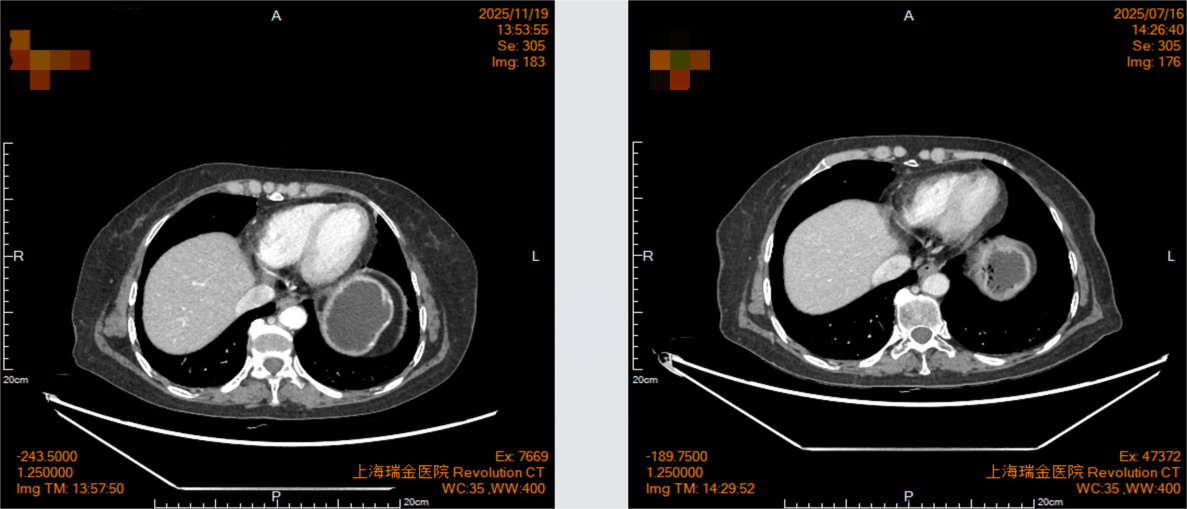

2025年7月16日复查影像学显示,贲门癌化疗后,贲门胃壁稍增厚;双肺间质性改变。

2025年11月19日复查影像学显示,贲门癌化疗后,贲门胃壁稍增厚;贲门部肿物及转移淋巴结较前明显退缩,影像表现为接近CR(无可评价病灶)。